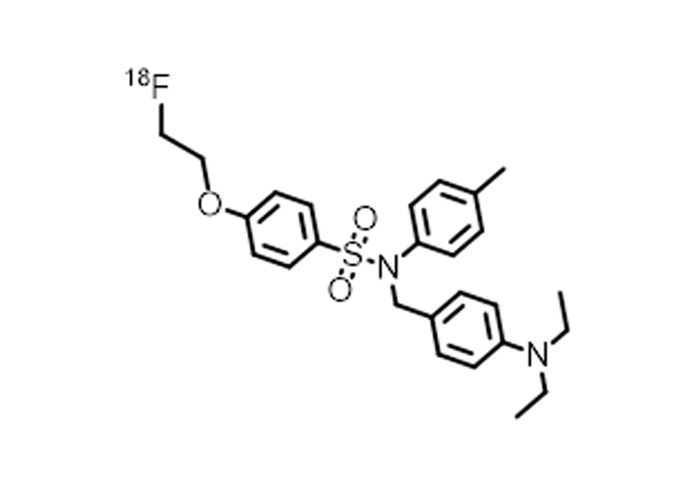

對(duì)18F、11C、68Ga、等核素示蹤劑的(de)合成與國(guó)外(wài)主流示蹤劑合成平台達到(dào)同一(yī)水(shuǐ)<平;

公司的(de)核心産品有(yǒu)先進的(de)放(fàng)射性藥物(wù)自(zì)動合成系統的(de)設計(jì)和(hé•)制(zhì)造,以及PET示蹤劑的(de)設計(jì)、合成及生(shēng)産。